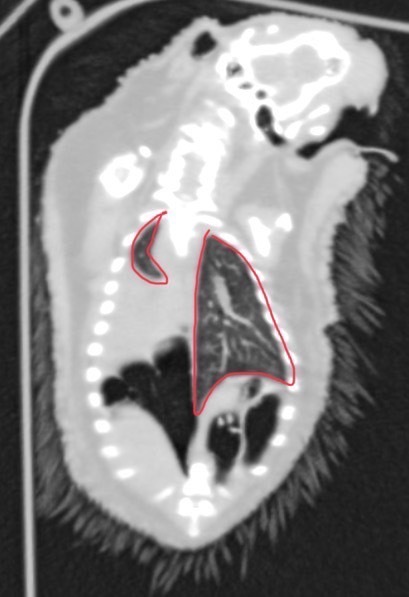

診断にはX線検査を用いて肺の透過性を確認するのですが、撮影時に丸まっている子も多く鮮明に肺を評価することが難しいこともあります。その場合はCT検査(基本的に麻酔は不要)にて評価をすることがあります。肺や鼻腔の細かい評価を行う際ら必要に応じでCT検査を提案させてもらっております。

左肺:正常の大きさ。右肺:肺炎からの無気肺で極小化